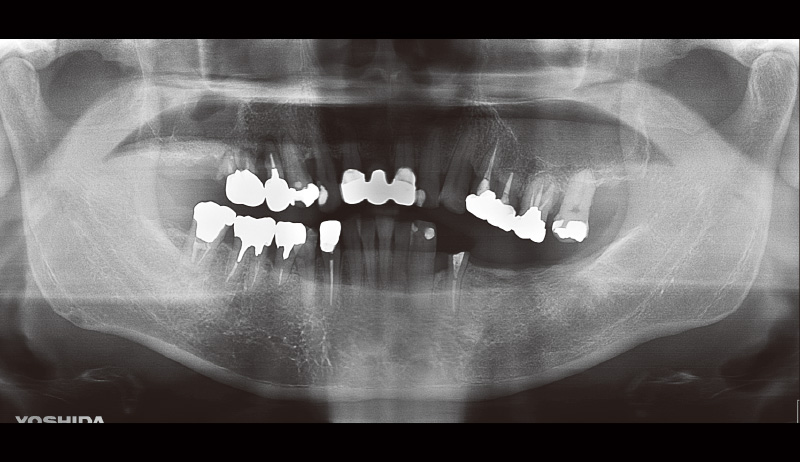

![[写真] 初診時のパノラマX線写真](/academic/dentalmagazine/wp-content/uploads/sites/2/2025/09/194-8_photo15.jpg)

図15 初診時のパノラマX線写真 -